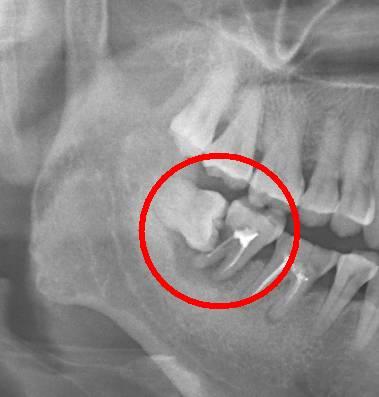

一般情況下,拔智齒就是把牙齦劃開,采用特殊的工具讓牙齒鬆動,然後慢慢的把上部的牙冠取出,一般情況下智齒的牙根還需要查看,因為(wei) 很多牙根需要再次進行鬆動後拔除的,而這些操作一般都是在局部麻醉下,進行的,所以基本上過程是不痛的,在術後可能會(hui) 有一些疼痛,不過一般都能忍耐,幾天後就會(hui) 恢複的。所以該拔的智齒還是要拔,不要因為(wei) 害怕疼痛就一拖再拖讓自己受罪。